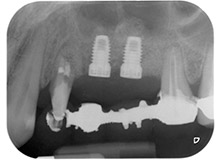

Fig. 1: 58-year-old patient. Preoperative radiograph showing an apical periodontal lesion at tooth 24 and horizontal loss of alveolar bone in the second quadrant.

A 58-year-old female patient complained of pain and increased mobility of her bridge abutment tooth 24. Periodontal inflammation was present with pocket depths of 7 mm mesiobuccally and more than 12 mm distally, as well as third-degree furcation involvement. Moreover, the radiograph revealed an extensive periodontal lesion around the apical region of the (alio loco) endodontically pretreated tooth 24 (Fig. 1).

Placement of two submerged implants was planned at sites 25 and 26, in a surgical session with open periodontal debridement and apicoectomy of tooth 24. Due to the vertical bone deficiency at the future implant site, an internal sinus augmentation was also planned.

Fig. 16: Postoperative radiograph showing the implants in place, with bone substitute material from the internal sinus lift around the apices. There is some material from the GTR procedure visible around the roots of tooth 24.